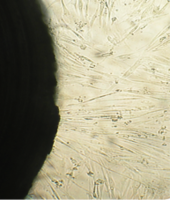

6 серия экспериментов. Образец исследуемого материала (аллогенный ГАП серии «Лиопласт»® массой 2 мг) помещали на дно культуральной чашки, после чего высевали фибробласты в стандартной концентрации.

Щелочной материал резко ухудшает прикрепление фибробластов к дну культуральных чашек (рис. 35) на всей его площади, вместе с тем прикрепившиеся клетки имеют четкие границы, нуклеолемма четко контурирует, цитоплазма гомогенная, без патологической зерностости, вакуолей и включений.

Рис. 35. Выраженная пролиферация, восстановление плотности монослоя.

Фибробласты лишь более распластаны по дну чашки, но это характерно для культуры с малой плотностью.

Вокруг образца через сутки от начала эксперимента клетки не прикрепляются (расстояние от края образца до границы 1,3±0,12 мм).

В последующие дни и до конца наблюдения плотность монослоя  в отдаленной от образца зоне нарастает даже несколько быстрее, чем в контроле, клетки сохраняют обычную для фибробластов в культуре морфологию.